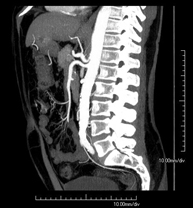

Prova diagnòstica no invasiva que consisteix en l'estudi de l'artèria aorta abdominal a través de l'obtenció d'imatges d'alta definició anatòmica mitjançant l'ús d'un equip de TC (Tomografia Computeritzada) i de contrast iodat. La qualitat de les imatges permet realitzar reconstruccions en 2D i 3D gràcies a estacions de treball especialitzades en l'estudi arterial. Està indicat en aquells pacients amb malaltia vascular (arteriosclerosi), en aneurismes d'aorta, en pacients amb dolor abdominal de possible origen vascular, en estudis prequirúrgics de lesions adjacents a l'aorta abdominal com a "mapa" vascular. La informació obtinguda de manera no invasiva és indispensable per als pacients que requereixen tractament percutani o quirúrgic. En aquells pacients que només requereixen seguiment de les lesions vasculars, aquesta tècnica és la tècnica no invasiva d'elecció juntament amb l'angio-RM. - Angio-TC Artèries renals

Prova diagnòstica no invasiva que consisteix en l'estudi de les artèries renals a través de l'obtenció d'imatges d'alta definició anatòmica mitjançant l'ús d'un equip de TC (Tomografia Computeritzada) i de contrast iodat. La qualitat de les imatges permet realitzar reconstruccions en 2D i 3D gràcies a estacions de treball especialitzades en l'estudi arterial. Està indicat en aquells pacients amb malaltia vascular (arteriosclerosi), en aneurismes d'aorta, en pacients amb dolor abdominal de possible origen vascular, en estudis prequirúrgics de lesions adjacents a l'aorta abdominal com a "mapa" vascular. La informació obtinguda de manera no invasiva és indispensable per als pacients que requereixen tractament percutani o quirúrgic. En aquells pacients que només requereixen seguiment de les lesions vasculars, aquesta tècnica és la tècnica no invasiva d'elecció juntament amb l'angio-RM. - Angio-TC Aorto-ilíac

Prova diagnòstica no invasiva que consisteix en l'estudi de les artèries ilíaques i l'aorta abdominal a través de l'obtenció d'imatges d'alta definició anatòmica mitjançant l'ús d'un equip de TC (Tomografia Computeritzada) i de contrast iodat. La qualitat de les imatges permet realitzar reconstruccions en 2D i 3D gràcies a estacions de treball especialitzades en l'estudi arterial. Aquesta prova està especialment indicada com estudi prequirúrgic (mapa vascular) abans d'intervencions percutànies o quirúrgiques d'aorta abdominal, com l'estudi complementari en pacients amb isquèmia de membres inferiors, etc. - Colonoscòpia virtual

Prova diagnòstica no invasiva que consisteix en l'estudi de l'artèria aorta abdominal amb l'obtenció d'imatges d'alta definició anatòmica mitjançant l'ús d'un equip de TC (Tomografia Computaritzada) i contrast iodat. La qualitat de les imatges permet realitzar reconstruccions en 2D i 3D gràcies a estacions de treball especialitzades en l'estudi arterial. Està indicat en aquells pacients que pateixen malaltia vascular (arteriosclerosi), aneurismes d'aorta, en pacient amb dolor abdominal d'un possible origen vascular, en estudis prequirúrgics de lesions adjacents a l'aorta abdominal com el "mapa" vascular, etc. La informació obtinguda de forma no invasiva és indispensable per als pacients que requereixen tractament percutani o quirúrgic. En aquells pacients que només requereixen un seguiment de les lesions vasculars, aquesta tècnica és la tècnica no invasiva d'elecció juntament amb l'angio RM. - Angio TC d'artèries renals

Prova diagnòstica no invasiva que consisteix en l'estudi de les artèries renals amb l'obtenció d'imatges d'alta definició anatòmica mitjançant l'ús d'un equip de TC (Tomografia Computaritzada) i contrast iodat. La qualitat de les imatges permet realitzar reconstruccions en 2D i 3D gràcies a estacions de treball especialitzades en l'estudi arterial. Aquesta prova està indicat en aquells pacients que pateixen HTA refractària al tractament, en pacients amb lesions renals que tenen un mapa vascular prequirúrgic, etc. - Angio TC d'aorta-ilíaca

Prova diagnòstica no invasiva que consisteix en l'estudi de les artèries ilíaques i l'aorta abdominal amb l'obtenció d'imatges d'alta definició anatòmica mitjançant l'ús d'un equip de TC (Tomografia Computaritzada) i contrast iodat. La qualitat de les imatges permet realitzar reconstruccions en 2D i 3D gràcies a estacions de treball especialitzades en l'estudi arterial. Aquesta prova està especialment indicada com a estudi prequirúrgic (mapa vascular) abans d'intervencions percutànies o quirúrgiques d'aorta abdominal, estudi complementari en pacients amb isquèmia de membres inferiors, etc. - Angio TC arterial d'extremitats inferiors